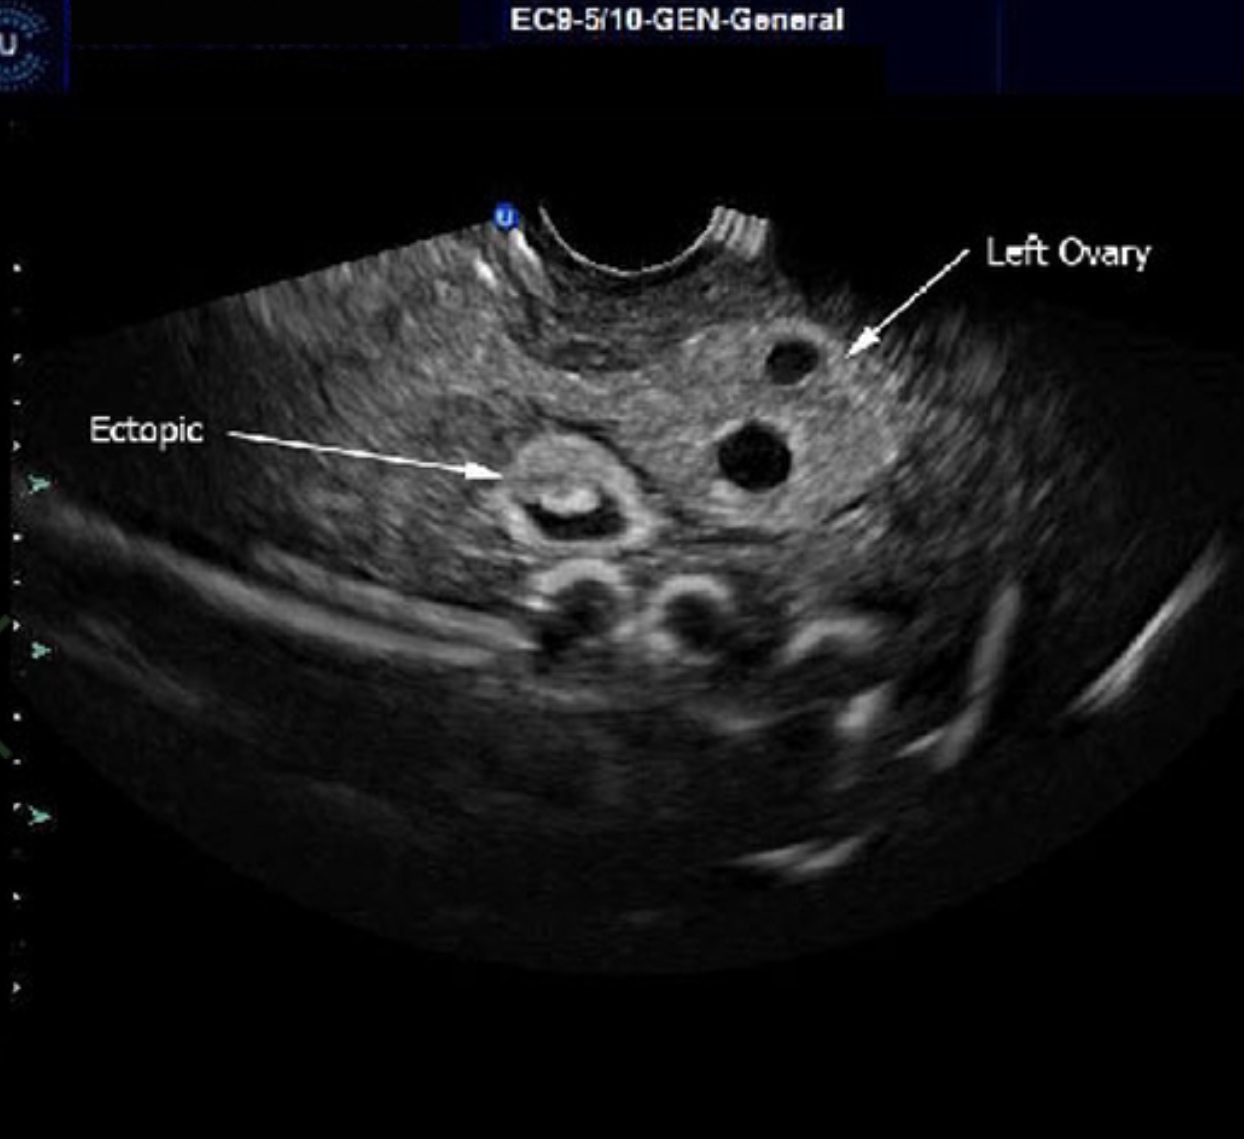

Modelo de anatomía pélvica femenina, con perineo y vagina realistas, que presenta estructuras internas como la vagina, el útero, el cérvix, las trompas de Falopio, los ovarios, la vejiga y el recto. Incluye estructuras del embarazo temprano a las 7 semanas de gestación, como el útero, el saco gestacional, el embrión, las trompas de Falopio y los ovarios, y simula un embarazo ectópico en las trompas de Falopio. Facilita la formación en ecografías pélvicas y de embarazo ectópico por vía transabdominal y transvaginal utilizando equipos de ecografía reales.

Embarazo ectópico: Contiene un saco gestacional de 7 semanas ubicado en la porción ampular de la trompa de Falopio, incluyendo el saco amniótico y la placenta, con características de la vagina y el cuello uterino, la vejiga y la pared vesical, el útero y la reacción pseudodecidual endometrial, la acumulación de líquido en la fosa uterino-rectal (bolsa de Douglas), los ovarios y folículos izquierdo y derecho, los quistes del cuerpo lúteo, el ligamento ancho del útero, el recto, el colon y otras estructuras accesorias, presentando imágenes ecográficas realistas.